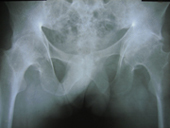

30 years old lady presented with complaint of pain right hip since 7 yrs and getting worse since 1 month. She is unable to walk and stand for a long time.

On examination she is having a painful limp, shortening of right lower limb, her hip movements are restricted and painful.

Xray showed evidence of old perthes disease and secondary osteoarthritis of right hip.

Hip Arthritis

In view of her young age , an uncemented Total Hip Replacement was carried out.

Hip Arthritis Uncemented Replacement

Post operative period was uneventful and she is walking painfree from 2nd post operative day .